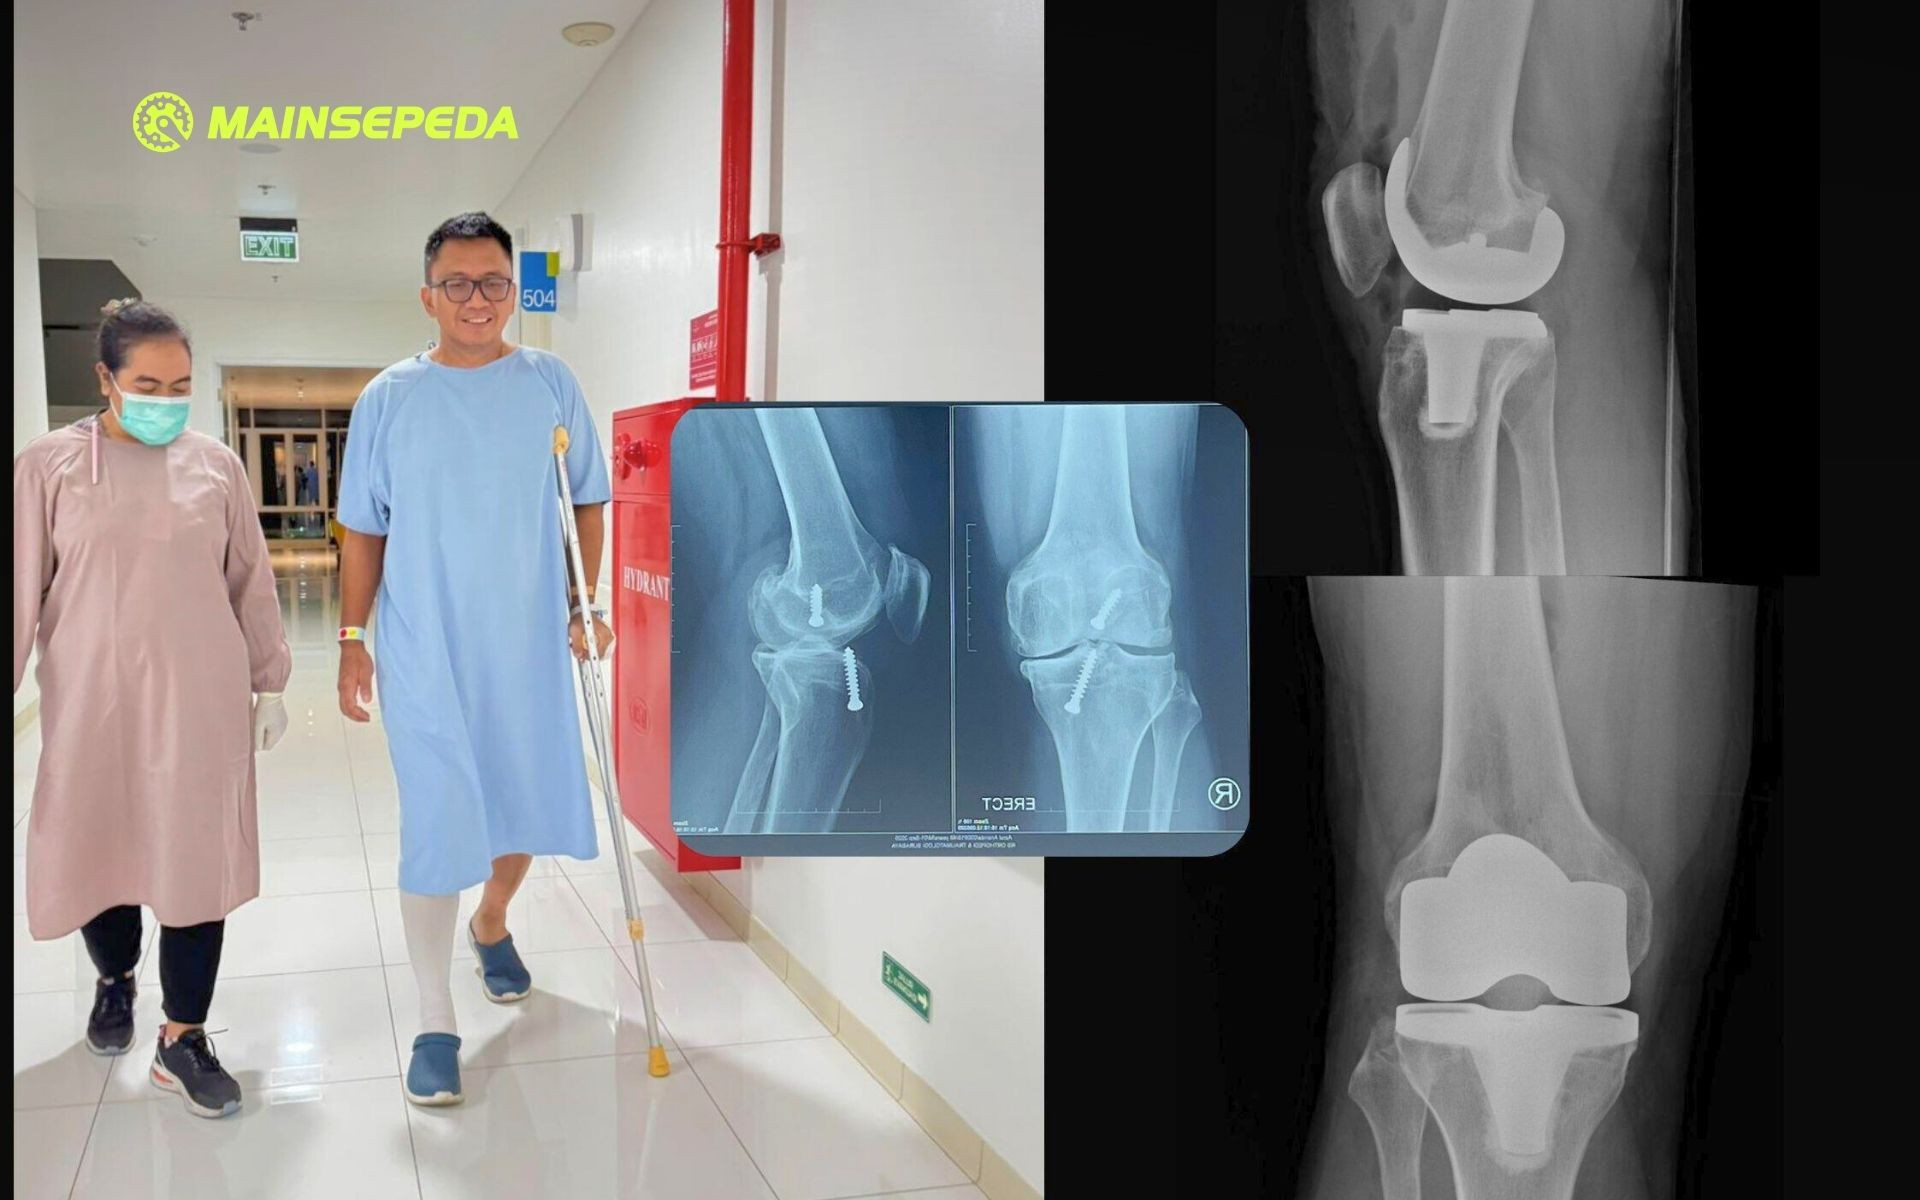

Alhamdulillah, operasi lancar. Kamis sore masuk RS Orthopedi Surabaya untuk persiapan, Jumat pagi jam 6 mulai menjalani prosedur sekitar empat jam. Saya masuk ruang operasi sangat semangat. Sangat tidak sabar segera punya lutut baru.

Sabtu pagi sekitar jam 09.00, sekitar 24 jam setelah operasi, saya sudah belajar jalan menggunakan walker empat kaki. Sabtu siangnya, saya sudah belajar jalan pakai dua kruk.

Minggunya, saya sudah belajar jalan pakai satu kruk. Latihan gerakan juga dilakukan, walau masih ada batasan-batasan.

Senin sebelum tengah hari, hanya tiga hari setelah operasi, saya sudah pulang ke rumah. Tinggal melakukan program pemulihan dan penguatan. Tentu juga melatih lagi gerakan-gerakan besar. Saya tak sabar segera bisa melipat lutut saya ke belakang lagi. Sudah lebih dari sepuluh tahun tidak bisa begitu!